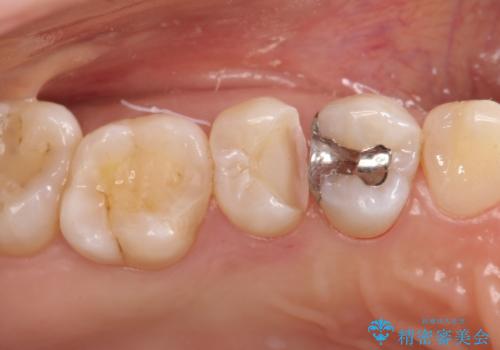

【セラミックインレー】むし歯の治療

- 定期検診にてむし歯を認めたため、セラミックインレーにて修復を行いました。

e-max プレスインレーにて修復治療を行っているため適合性及び審美性の高い治療を行うことができます